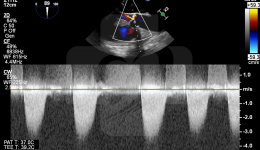

2019年第三届全国负荷超声心动图及心血管超声造影学习班在巴蜀之都盛大开幕,本次学习班由四川省人民医院心血管超声及心功能科尹立雪教授带领的心血管超声专业团队主办,届时也邀请到山东大学齐鲁医院张梅教授、北京大学人民医院朱天钢教授、空军军...